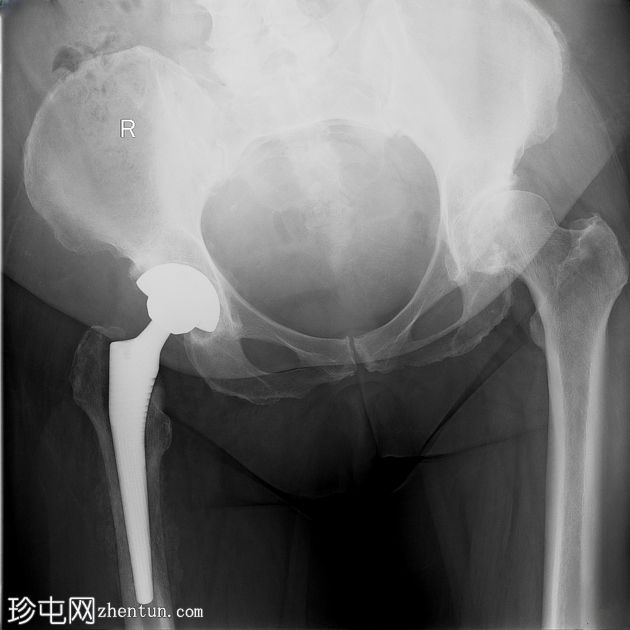

全髋关节置换术后慢性骨髓炎

患者因左髋全髋关节置换术后3个月内疼痛进行性加重而就诊。术后早期伤口化脓性分泌物并发,经验性抗生素治疗后缓解。目前,患者持续疼痛,夜间疼痛明显加剧,功能障碍严重,患肢无法负重,需借助助行器行走。

X光片

正面

右侧股骨骨干近端1/3可见明显的骨皮质变形,并伴有环状骨膜反应。内侧和腹侧表面可见边界清晰的椭圆形透亮区,最大直径约1厘米和2厘米,为骨皮质渗透区。

病例讨论

假体周围感染是全关节置换术后严重且棘手的并发症,在初次手术中的发生率约为 1-2%。术后早期伤口感染,尤其是伴有化脓性分泌物的感染,若未得到充分治疗,是后期发展为慢性骨髓炎的重要危险因素。

在本例中,尽管最初使用抗生素治疗后感染似乎得到缓解,但患者仍出现持续性局部疼痛和慢性骨受累的放射学征象,包括骨膜反应和可能的松动。

这些发现提示慢性骨髓炎,这是一种细菌在骨内持续感染的疾病,通常由于假体等异物的存在和细菌生物膜的形成而加剧。影像学检查中出现的透亮病灶进一步支持了诊断,反映了持续感染导致的骨皮质浸润。